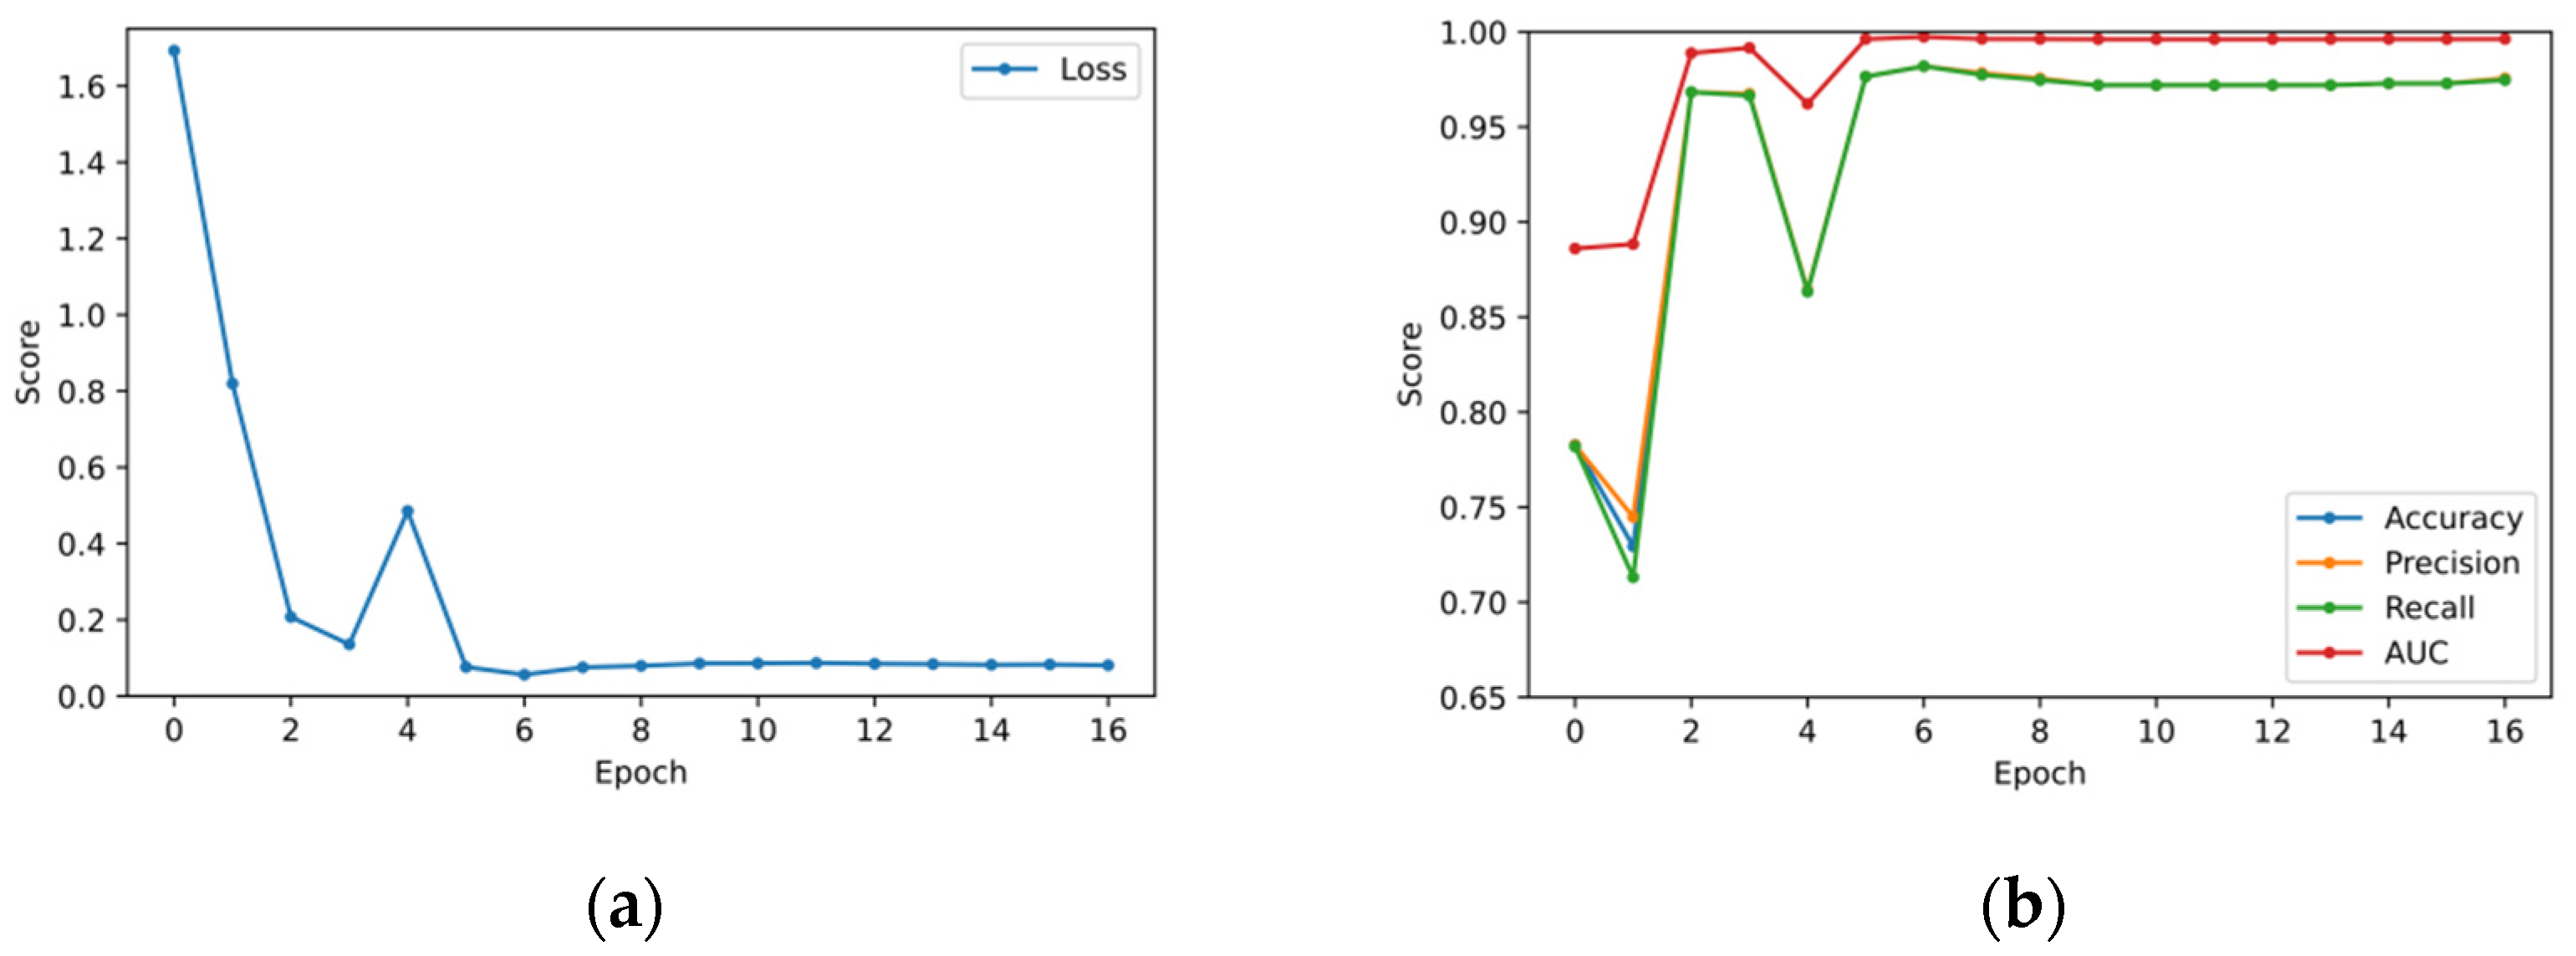

5.2. Validation Set Results

5.3. Test Set Classification Results